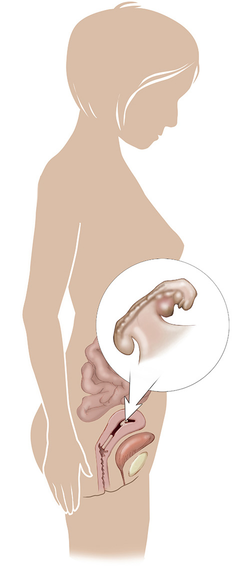

ما هو الحمل خارج الرحم؟

الحمل خارج الرحم هو إنزراع ونمو البويضة المخصبة خارج الرحم ما يسبب الوفاة لحوالي 13% من الحالات ... المزيد